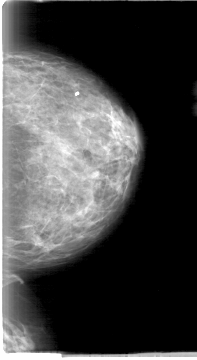

D_4013_1.LEFT_MLO

D_4013_1.LEFT_CC

LEFT_MLO LINES 5386 PIXELS_PER_LINE 3031 BITS_PER_PIXEL 12 RESOLUTION 43.5 NON_OVERLAY

LEFT_CC LINES 5386 PIXELS_PER_LINE 2941 BITS_PER_PIXEL 12 RESOLUTION 43.5 NON_OVERLAY